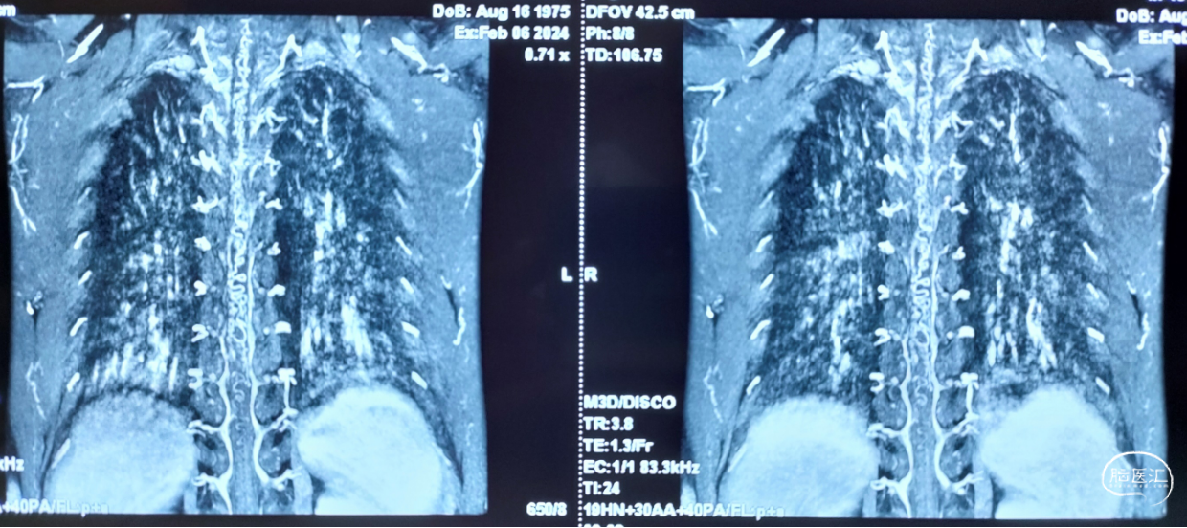

术后4天影像(2024-02-26, 本院)

image.png

术后1月影像(2024-03-28, 本院)

显微镜下探查瘘口多位于神经根附近的硬脊膜上,烧闭并切断瘘口处血管即可,脊髓异常引流静脉会逐渐自动消失,脊髓张力会随之下降。